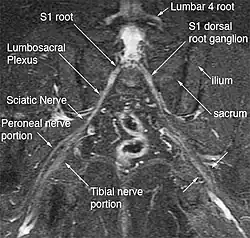

Anatomy

The hip has five external rotators: The piriformis, superior gemellus, obturator internus, inferior gemellus, and quadratus femoris. (External rotation is an anatomical term of motion to describe rotation away from the center of the body.) The inferior gluteal nerve/artery, sciatic nerve, pudendal nerve, posterior femoral cutaneous nerve, obturator internus nerve, superior gemellus nerve, quadratus femoris nerve, and inferior gemellus nerves exit the greater sciatic foramen underneath the piriformis.[6][4] While any of the nerves which exist in this deep gluteal space can be entrapped by deep gluteal space problems, the existing definition of the syndrome tends to focus on sciatic nerve pathology specifically.